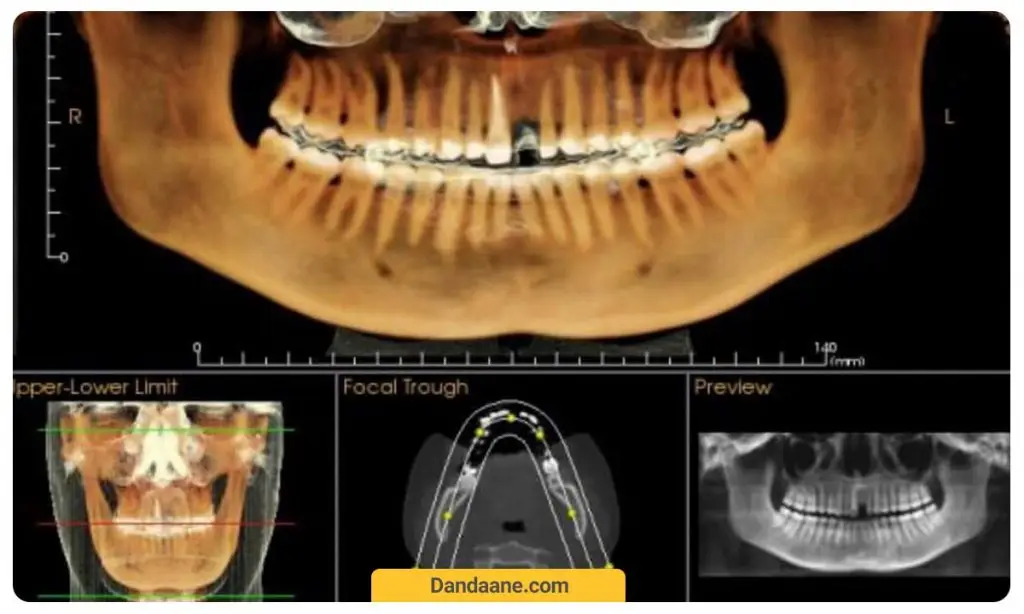

توموگرافی 3 بعدی یا CBCT

از عکس دندان CBCT معمولا برای تشخیص مشکلات استخوان های فک استفاده می شود. مثلا می توان برای تشخیص شکستگی ها یا تومورهای فک این تصاویر را بررسی و تفسیر کرد. عکس سی تی اسکن به صورت خاص می تواند وضعیت استخوان فک را پیش از کاشت ایمپلنت دندان یا جراحی های کشیدن دندان چک کرد تا از بروز عوارض احتمالی طی عمل و حتی بعد از آن اجتناب کرد.

قیمت عکس دندان سی بی سی تی معمولا بیشتر از هزینه عکس opg دندان است. (240 هزارتومان)